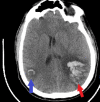

Figure 3. Computed tomography of the head (axial view).

Left frontoparietal intraparenchymal hematoma measuring 37 mm × 57 mm.

Figure 4

Figure 4. Computed tomography of the head (axial view).

The blue arrow shows the right parietal lobe intraparenchymal hematoma, and the red arrow shows the left frontoparietal intraparenchymal hematoma.